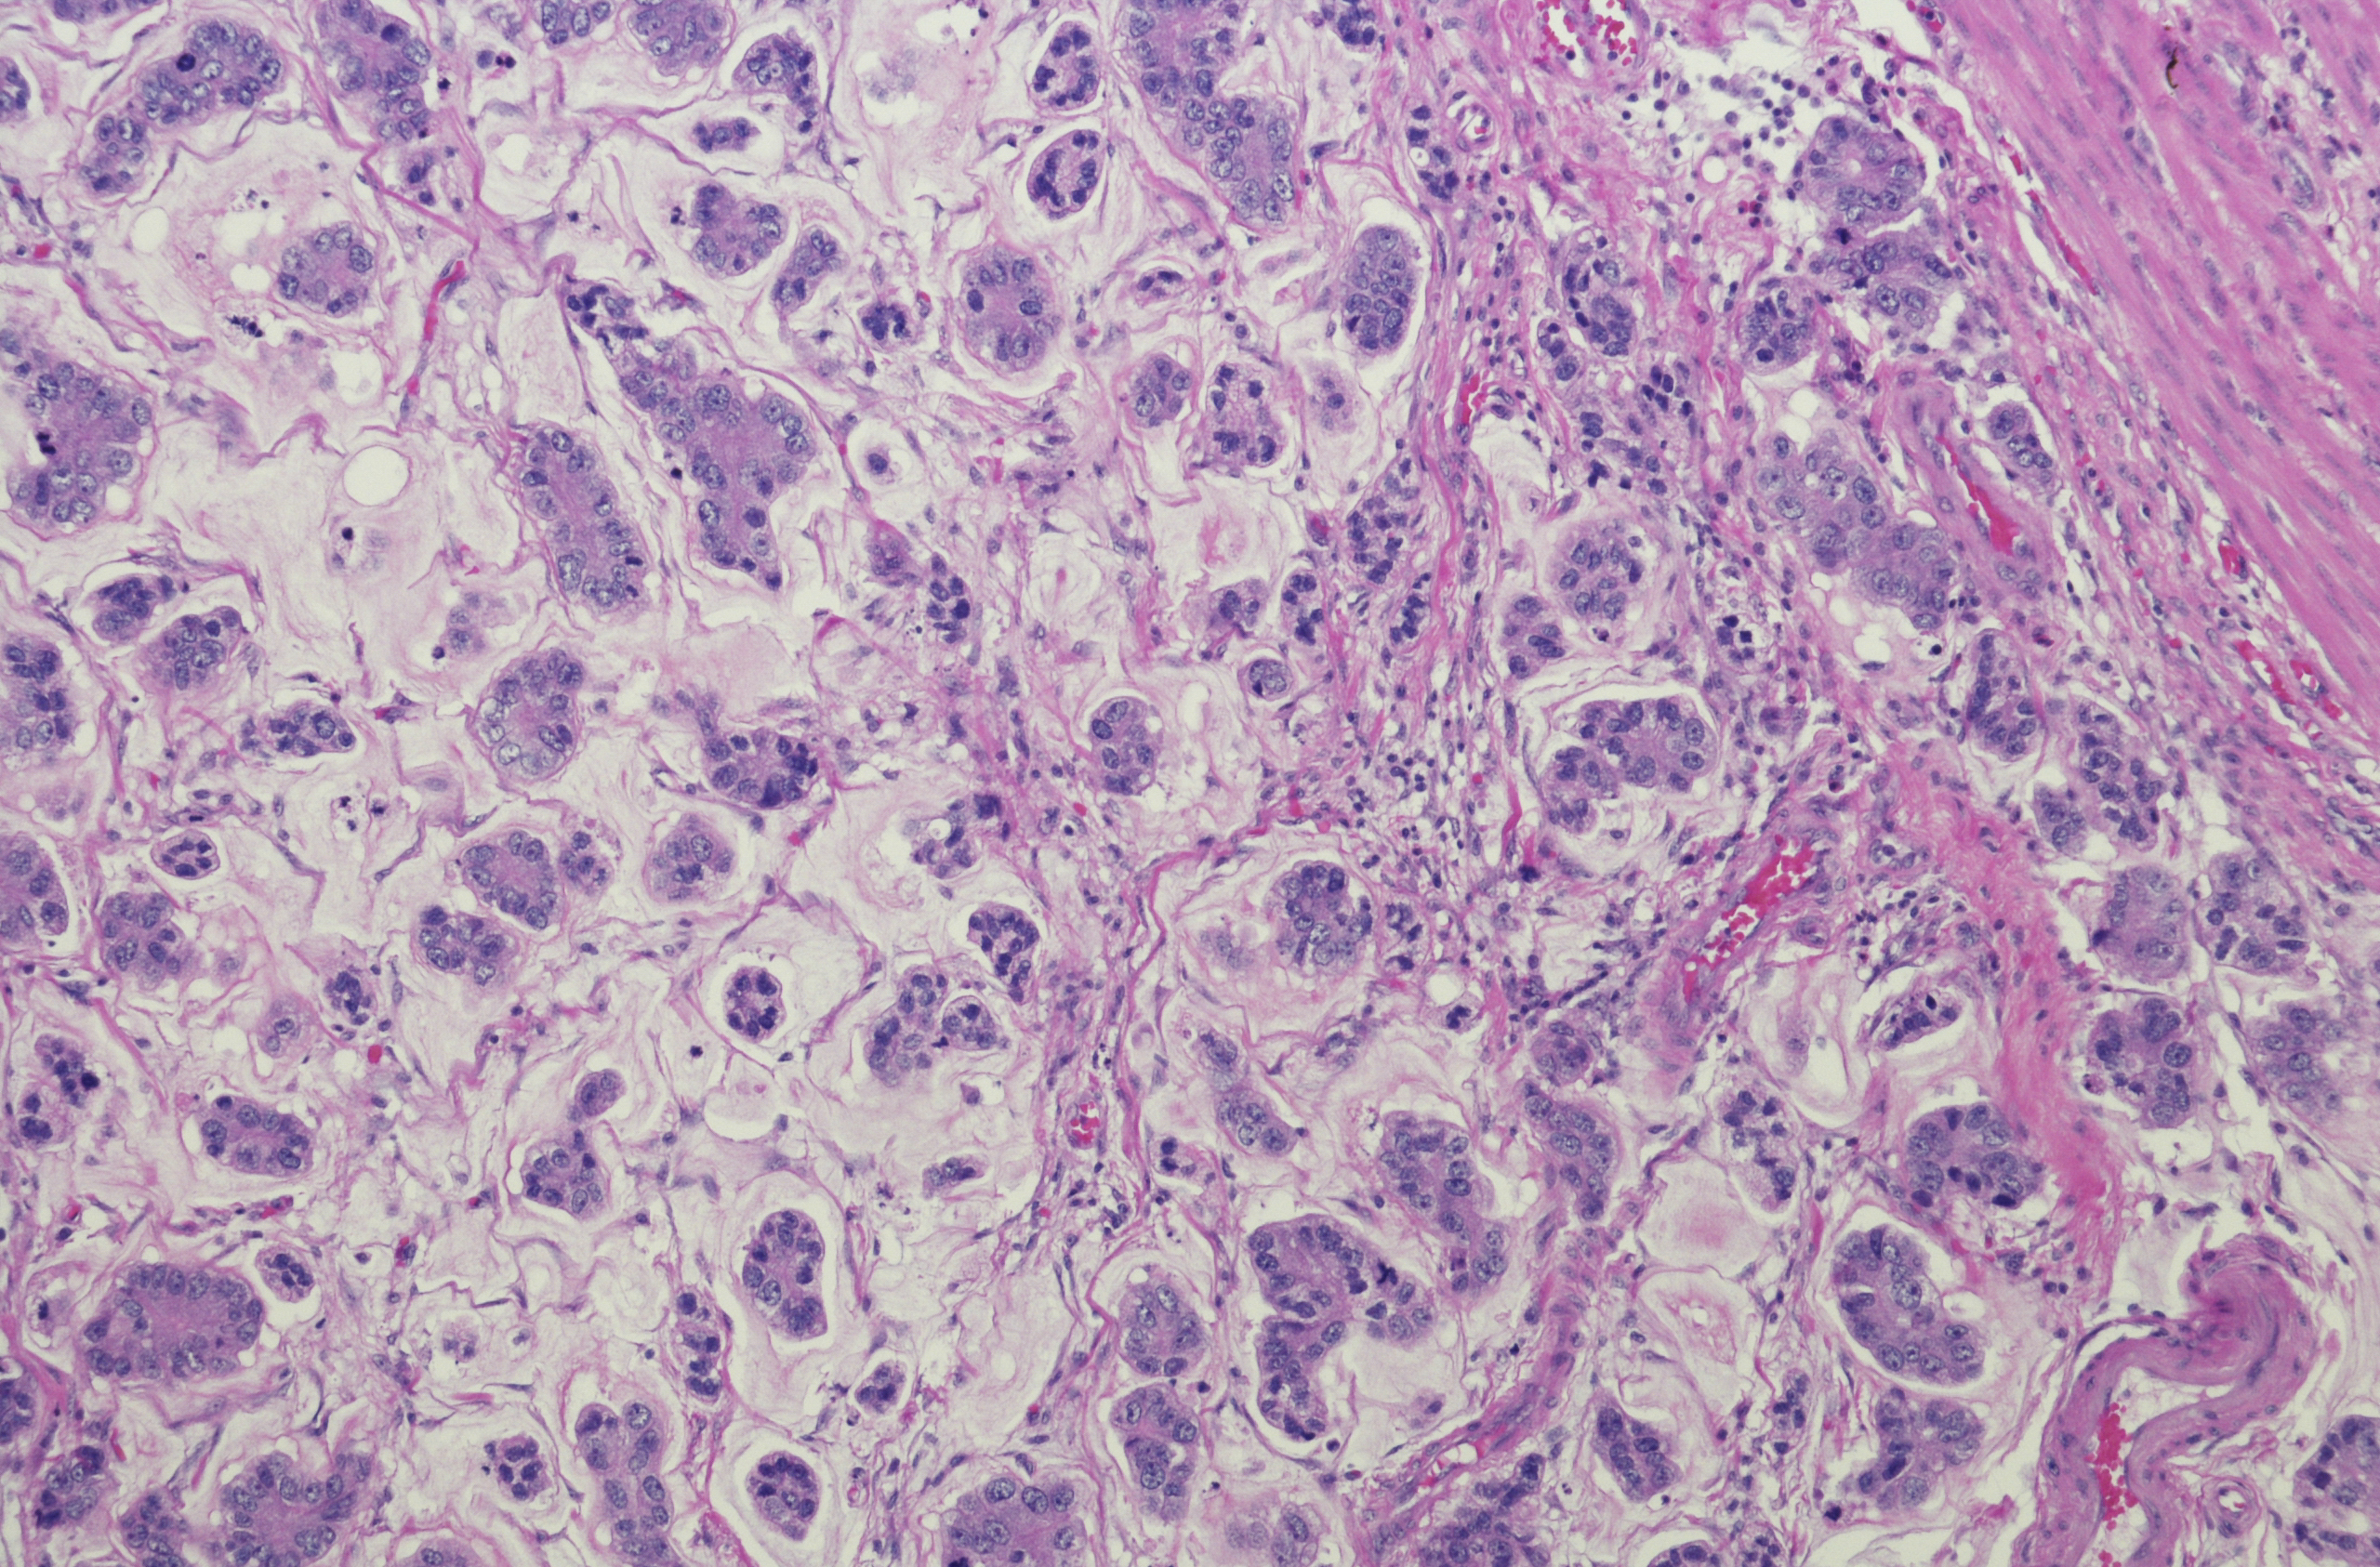

Around 90 to 95 per cent of Stomach Cancers develop in cells lining the mucosa – these are called adenocarcinomas, and they spread through the outer layers of the stomach. Other types include squamous cell carcinoma, lymphoma, stromal tumours, and carcinoid tumours, however these are rare.